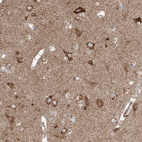

Immunohistochemical staining of human cerebral cortex shows strong cytoplasmic positivity in neurons.